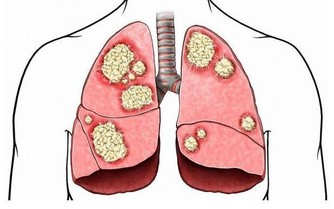

2、無尿

如果我們體內的尿酸過高,體內就會出現結晶,腎小管可能因此被堵塞,造成無尿的現象。如果經常這樣,我們體內的毒素不能排出,就會積累在身體內,久而久之,就會威脅身體健康。